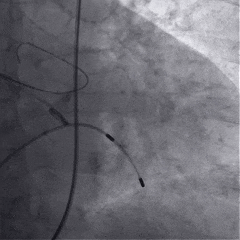

术中影像

根部造影

球囊预扩

瓣膜稳定释放

瓣膜展开后造影

再次造影,确认瓣膜位置

稳定脱钩

最终造影,瓣膜位置良好,无明显瓣周漏

外周血管检查